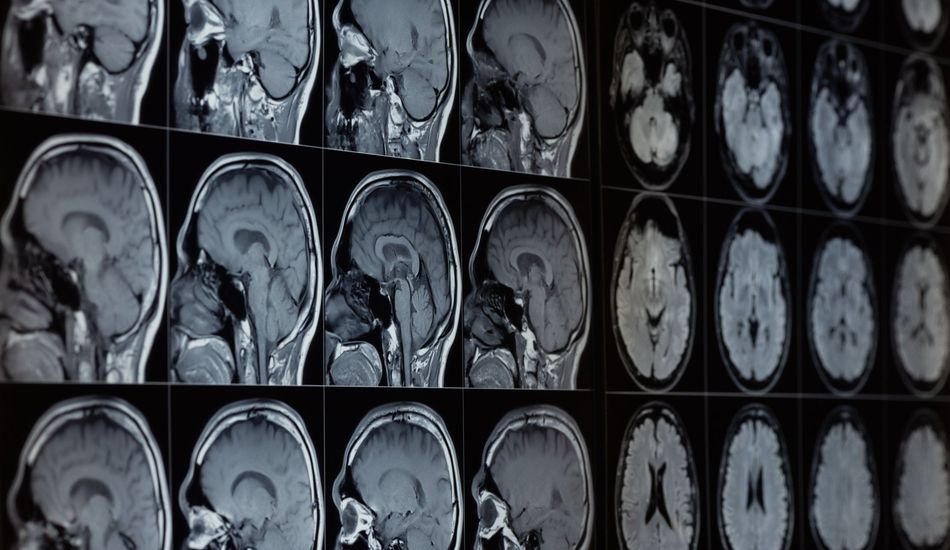

O Alzheimer é uma doença devastadora e, mesmo com o progresso que fizemos, os tratamentos só vão até certo ponto quando os sintomas aparecem. No entanto, uma nova pesquisa sugere um fator anteriormente negligenciado que pode impulsionar a doença, abrindo potencialmente portas para novas terapias. Será que pode ser tão simples assim?

Cientistas da Harvard Medical School encontraram evidências de que nossos cérebros contêm lítio naturalmente e que a falta dele pode contribuir para os danos causados pelo Alzheimer. Isso é muito importante, pois desafia a ideia de que o lítio é apenas uma droga que tomamos em altas doses para certas condições.

O estudo comparou amostras de cérebros de pessoas com diferentes graus de saúde cognitiva. O que eles descobriram foi bastante impressionante: pessoas com cérebros saudáveis tinham mais lítio do que aquelas com Alzheimer. Curiosamente, essa perda de lítio era visível mesmo em pessoas que apresentavam apenas pequenos problemas de memória.

Para investigar mais a fundo, os pesquisadores estudaram camundongos saudáveis e camundongos com uma versão da doença de Alzheimer. Quando diminuíram os níveis de lítio nos camundongos, pareceu acelerar o acúmulo de proteínas não saudáveis ligadas à doença, e a memória também diminuiu. Parece que as placas beta amilóides, aquelas marcas infames do Alzheimer, se ligam ao lítio do cérebro, fazendo com que ele desapareça. É quase como se a doença estivesse roubando um nutriente vital de nossos cérebros!